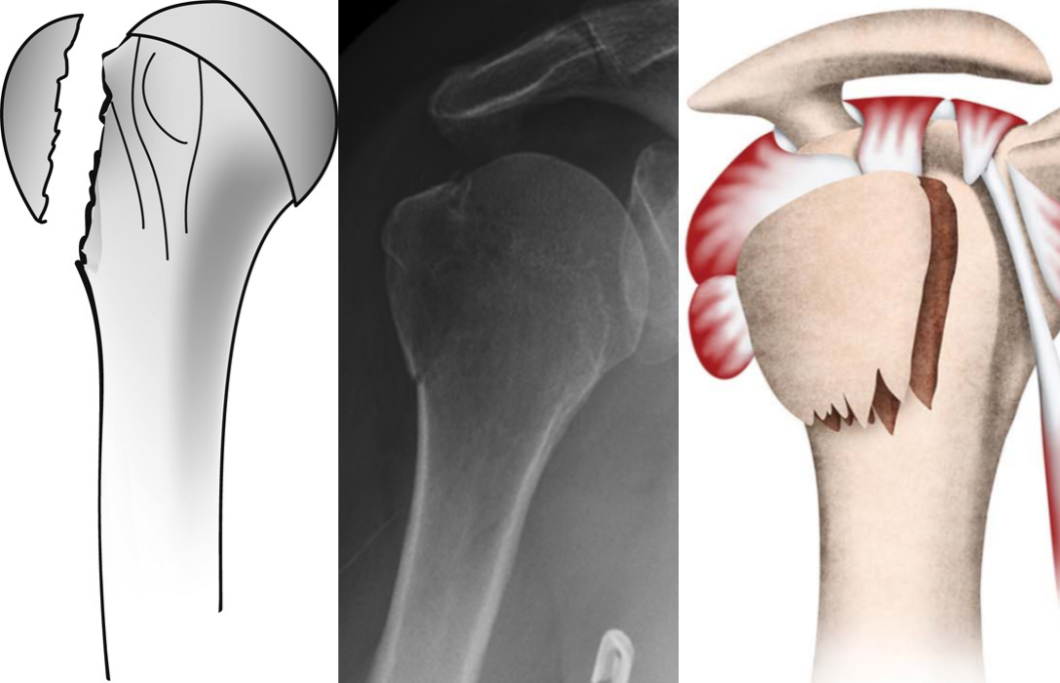

Bahrs等(2006年)提出大结节骨折的三种致伤机制:撕脱机制、肩峰撞击机制和关节盂缘撞击机制。Mutch等(2014年)在此基础上进一步提出基于骨块形态的分类系统:

压缩性骨折:因大结节与关节盂或肩峰撞击导致骨块向肱骨头内凹陷。

图5 doi:10.1302/0301-620X.96B5.32362